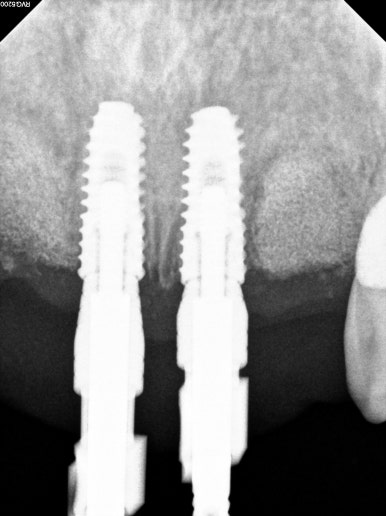

엑스레이를 보시면, 양쪽 위턱 가쪽 앞니가 거의 잇몸뼈와 분리되어 둥둥 떠있는 모습을 보실 수 있습니다.

잘 모르시겠다면, 제가 표시해드리겠습니다..!!

점선이 실제 잇몸뼈의 높이를 나타내고 있습니다.

노란 화살표로 표시한 두개의 위턱 측절치가 남아있는 뼈 없이 둥둥 떠있는 모양이에요.

남은뼈가 굉장히 적었기 때문에, 치과용 치근단방사선사진을 촬영해가며 그 위치를 설정하였습니다.